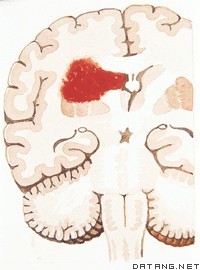

腦出血繼發丘腦下部損傷:①丘腦下部的解剖特點:丘腦下部包括丘腦下溝以下的第三腦室壁及室底上的一些結構,其中含有15對以上的神經核團,數以萬計的神經分泌細胞,如位於第三腦室壁上的室旁核、空周圍核、腹內側核、背內側核等,丘腦下部長約1cm,重約4g,約為全腦重量的3‰.但機制複雜,與植物神經、內臟活動。內分泌、代謝、情緒、睡眠和覺醒均有關。該區還有以下特徵:有豐富的毛細血管網,較腦的其他部分多一倍以上,且該處血腦屏障不夠健全,有較高的通透性,故在缺氧、中毒,顱壓增高、感染等損傷時易出現水腫和出出血等改變;漏斗柄是丘腦下部與垂體間的神經纖維聯繫,當其受壓、腫脹、出血時,該聯繫即遭到破壞。②丘腦下部損傷的臨床症狀:腦出血引起顱內壓增高,出現占位效應,致使丘腦下部受壓,垂體柄水腫、移位、扭曲等,加以繼發腦室出血損傷第三腦室壁均累及丘腦下部,出現症狀,常表現為出血性胃糜爛或潰瘍,嘔吐咖啡樣胃內容物,急性肺水腫,白細胞增高.血糖升高,中樞性高熱,大汗淋漓等。

腦出血繼發腦疝;腦出血可以並發天幕疝,中心疝、枕骨大孔疝、蝶骨嵴疝、扣帶回疝及小腦上疝。後三者一般不出現明顯的臨床症狀,多在剖檢時發現;前三者臨床症狀明顯,多為症狀加重或致死的原因。天幕沿時出現同側瞳孔散大。中心疝時雙側瞳孔均小呼吸不規則。其病理標誌為:①赤質、紅核向下移位,②第三腦室向下移位,(3)丘腦下部及上部腦幹向下移位。出現中心疝時,則很可能發生枕大孔疝,呼吸心跳解離,至死亡。